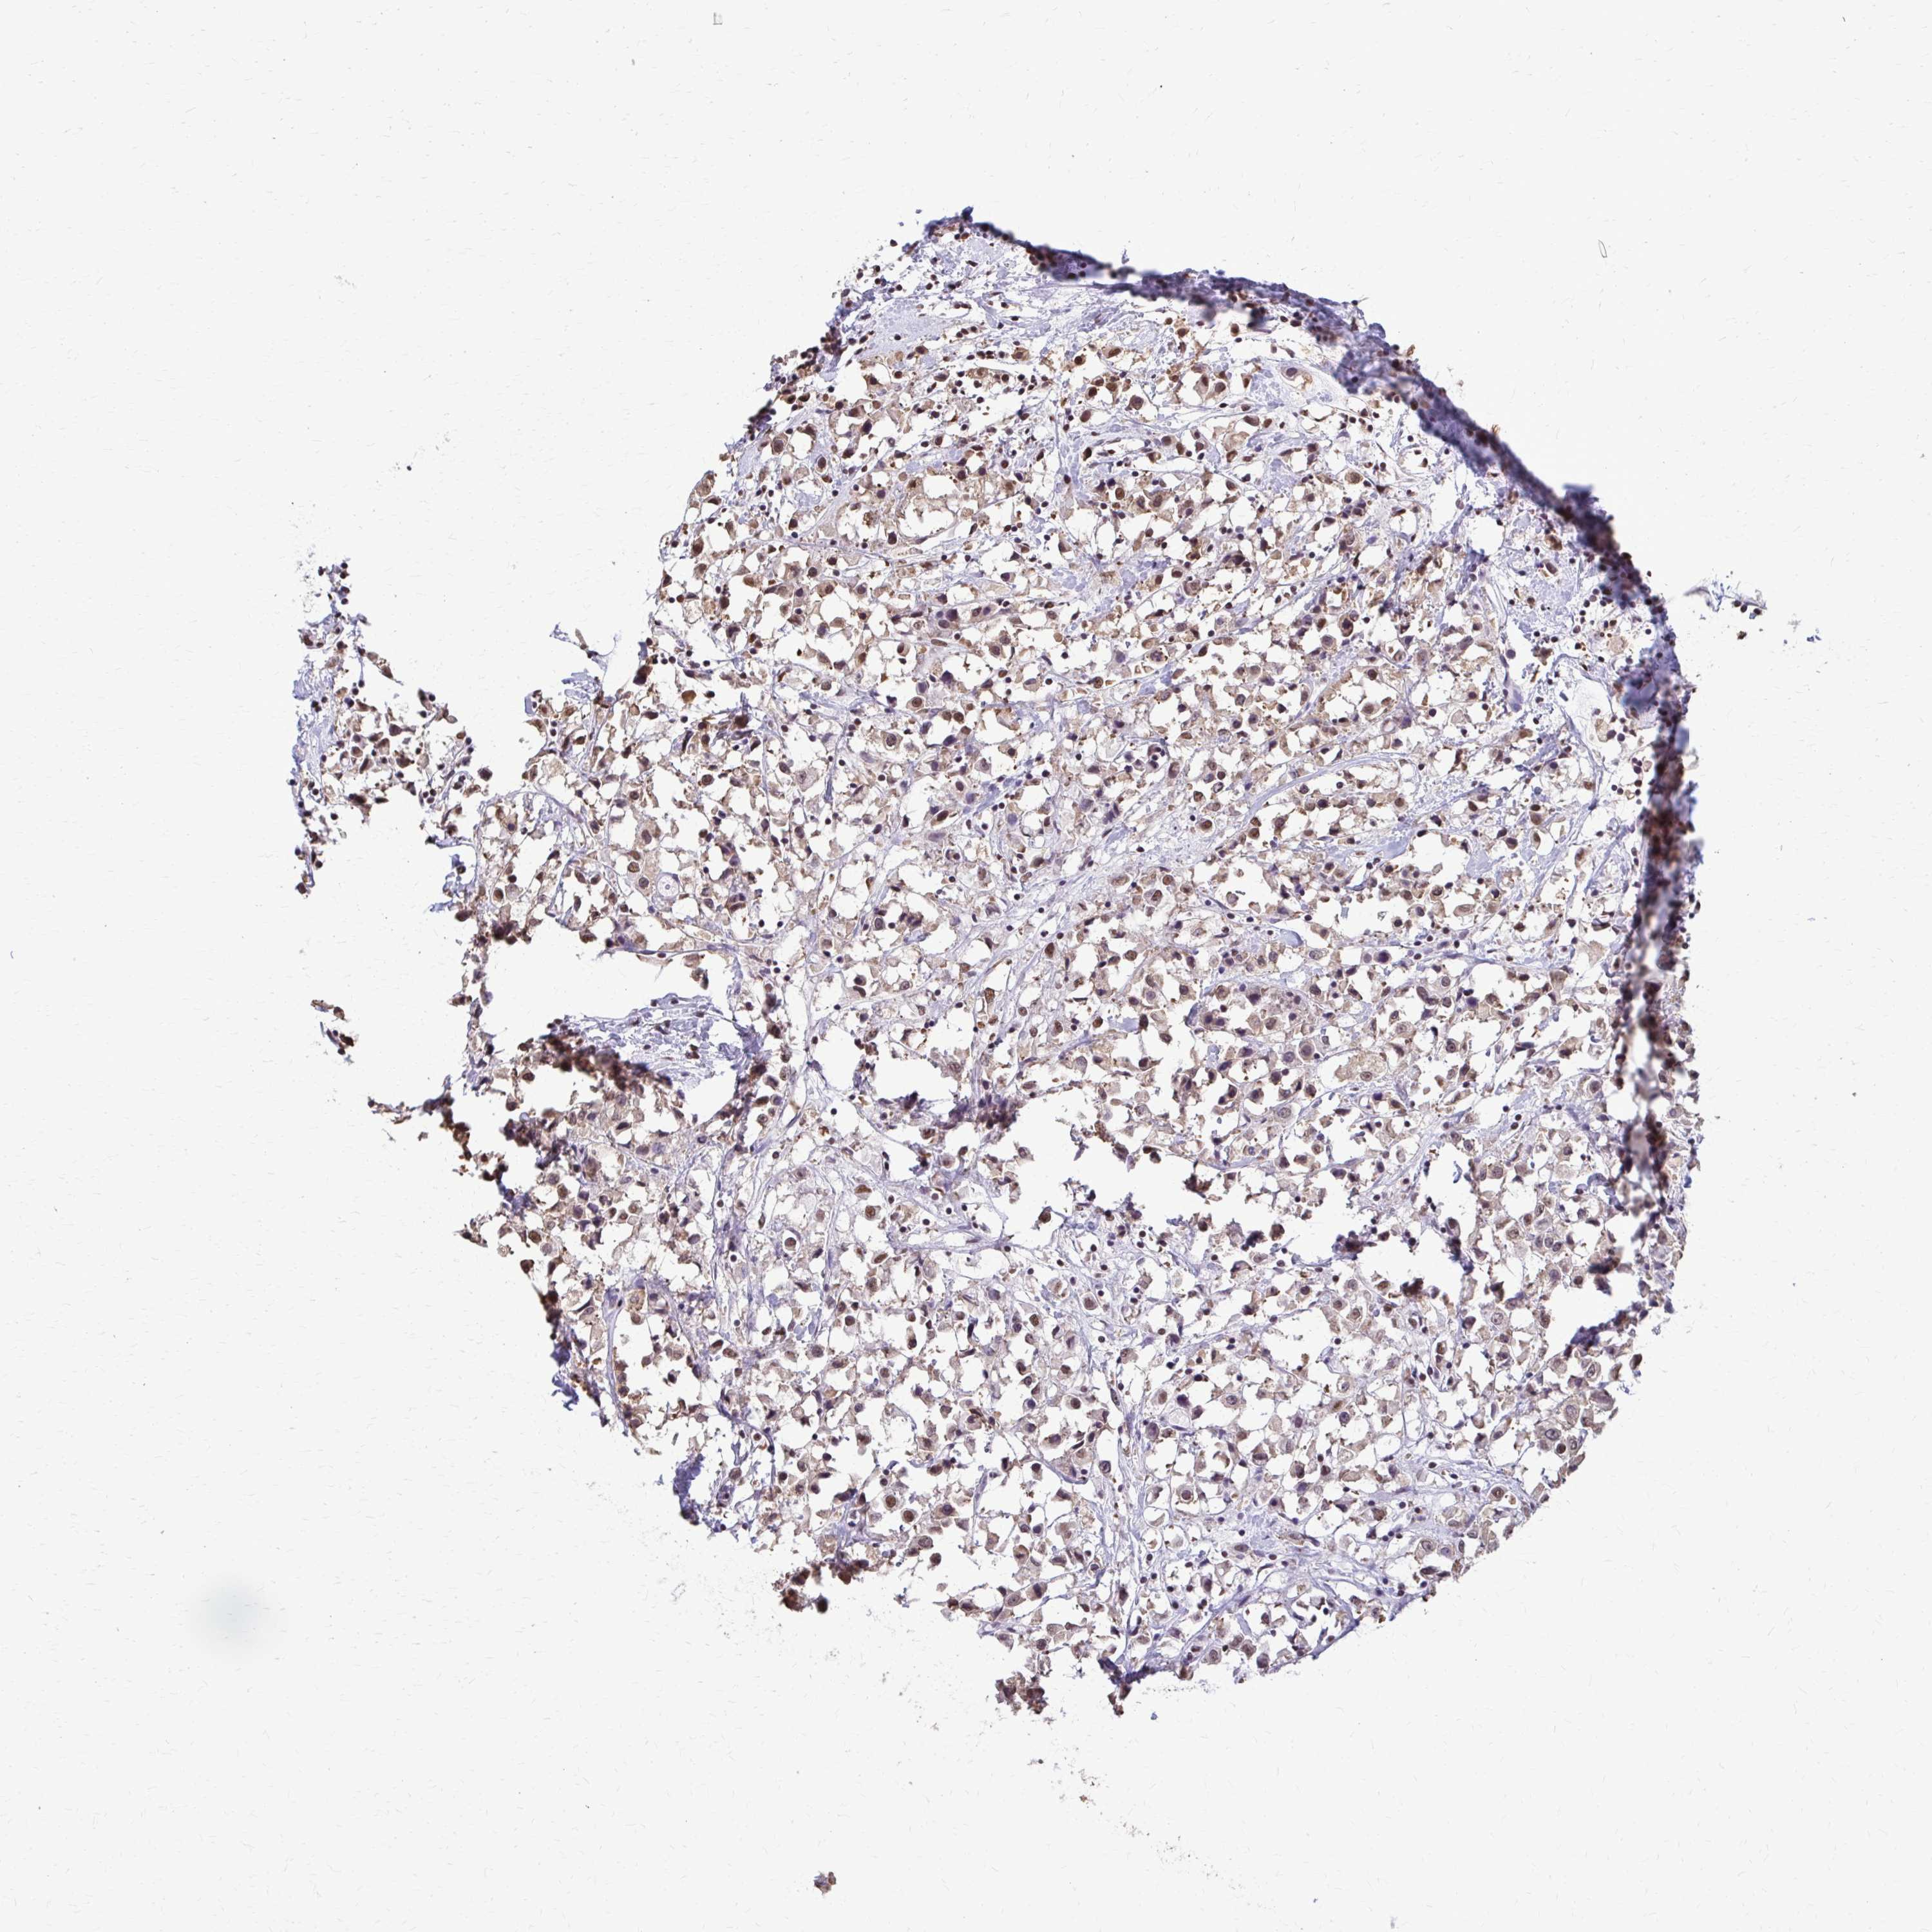

CANCER BREAST CANCER Show tissue menu

BRCA TCGA BRCA VALIDATION PROTEIN EXPRESSION